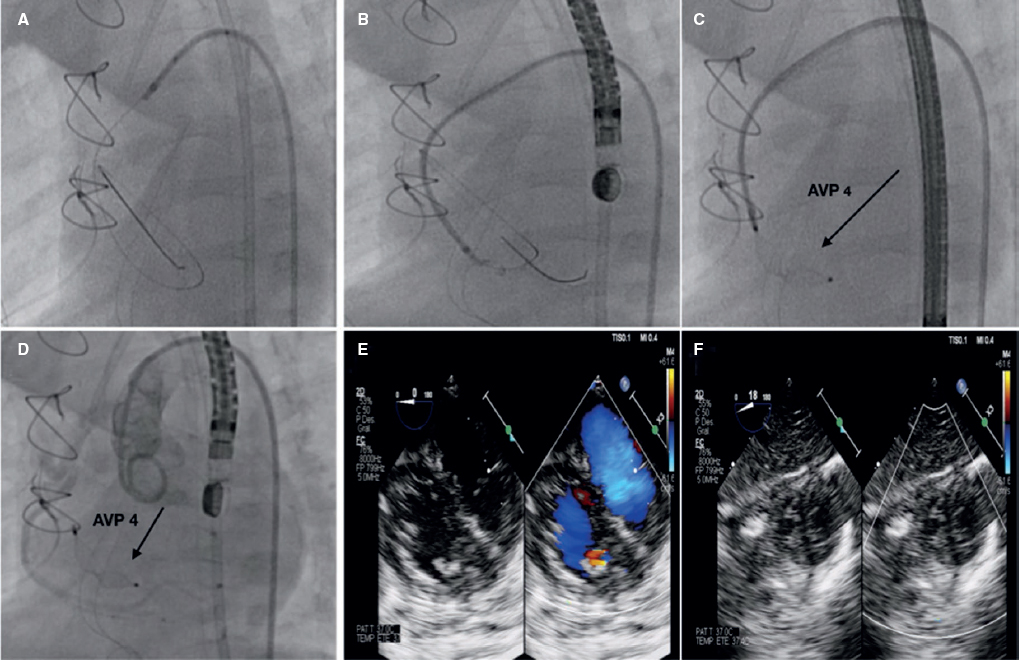

Varón de 70 años con hallazgo casual por ecocardiografía transtorácica y transesofágica de una gran masa en la aurícula derecha con abundante componente vascular, y tras su estudio con tomografía computarizada cardiaca se confirma el hallazgo de una malformación arteriovenosa. Se obtuvo el consentimiento informado del paciente para la difusión del caso. Se realiza estudio coronariográfico que muestra aferencia desde la coronaria derecha media hacia la masa auricular, por lo que se decide el cierre percutáneo. Este se lleva a cabo con microcatéter avanzado hasta la zona media de la rama aferente y protegiendo mediante inflado de balón de angioplastia en la coronaria derecha media. Se liberan 10 Hilal Coils (Cook Medical, USA), con buen resultado y cierre completo del defecto (figura 3).

Figura 3.